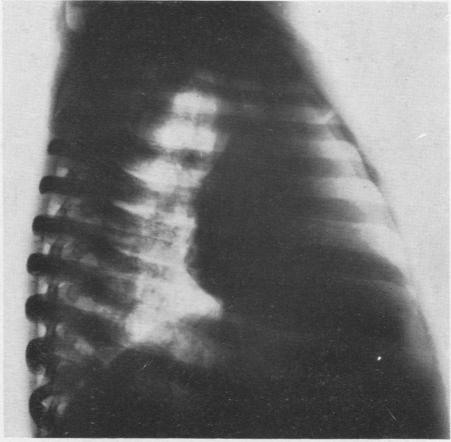

HARLEY H R S, DREW C E

Thorax. 1950 Jun;5(2):105-15. doi: 10.1136/thx.5.2.105.